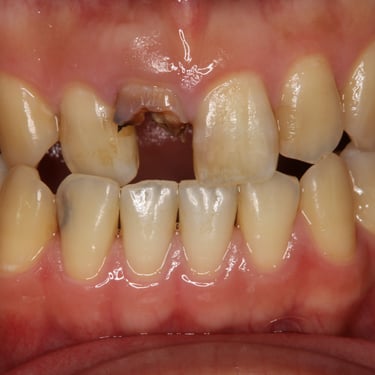

Pérdida de múltiples dientes

La pérdida de múltiples dientes es la ausencia de varios dientes que puede ser resultado de caries, enfermedades periodontales o traumatismos.

Los pacientes notan varios espacios vacíos en su boca, lo que afecta su capacidad para masticar y hablar adecuadamente.

El tratamiento incluye la colocación de varios implantes dentales para restaurar la función y la estética.